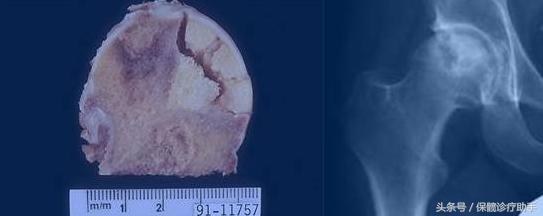

股骨头坏死早期往往是骨细胞已经坏死、骨小梁变形、萎缩,或已经有虫蚀样改变、点状硬化,股骨头的骨质已经如冻豆腐一般疏松,出现间隙,但是病人还没有什么症状。

等到病人出现髋部、腿部疼痛时,肢功能明显受限,无法盘腿,走路开始跛行,股骨头坏死往往已发展到中后期。